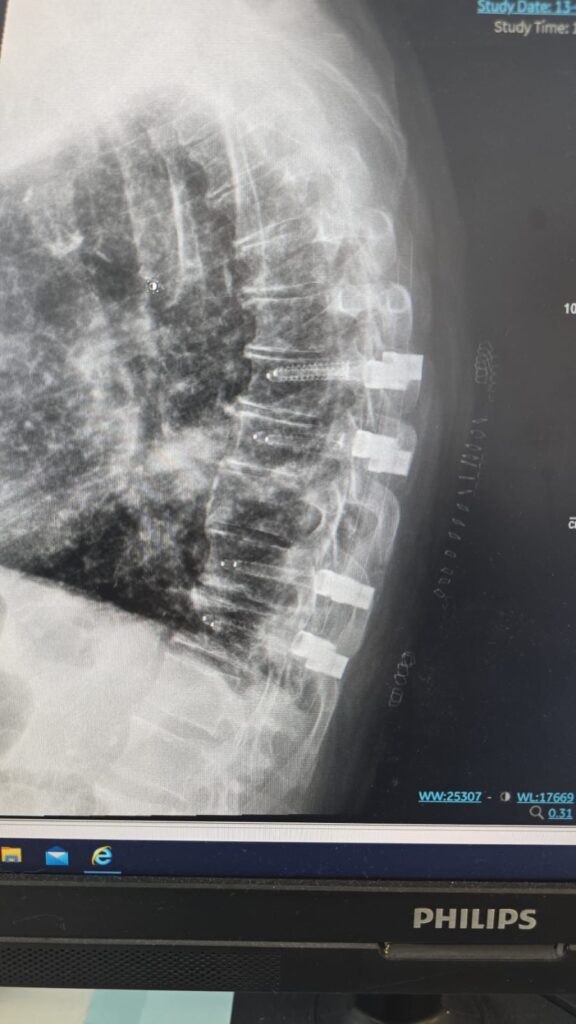

המטופל, גבר בן 60 שחלה בסרטן ריאה שפיתח גרורה בעמוד השדרה, הגיע למיון אסותא אשדוד כשהוא בסכנת שיתוק מיידית. במהלך הניתוח הוחדרו 8 ברגים ומוטות מקרבון בחיתוכים של כ־1 ס”מ בלבד, ובמקביל נכרת הגידול שגרם ללחץ על חוט השדרה. התוצאה הייתה דרמטית:

הטכניקה להכנסת ברגים בעמוד השדרה דרך חתכים זעירים אינה חדשה. למעשה, היא קיימת כבר כ־30 שנה ומשמשת בעיקר לטיפול בשברים בלתי יציבים. השיטה מבוססת על החדרת מחט לתוך החוליה בהנחיית שיקוף, הכנסת תיל מתכת עדין, הברגת הבורג למקומו המדויק, ולבסוף הכנסת מוט דרך אותם חתכים. השיטה מאפשרת ניתוח כמעט ללא דימום, זיהום מינימלי והחלמה מהירה.

ברגים ומוטות מקרבון אינם יוצרים הפרעות בהדמיות MRI, ומאפשרים לבצע בדיקות איכותיות גם לאחר הניתוח. בנוסף, הם מפחיתים משמעותית סיכונים בהקרנות-ומאפשרים לרופא האונקולוג לכוון את הקרינה בדיוק רב יותר.